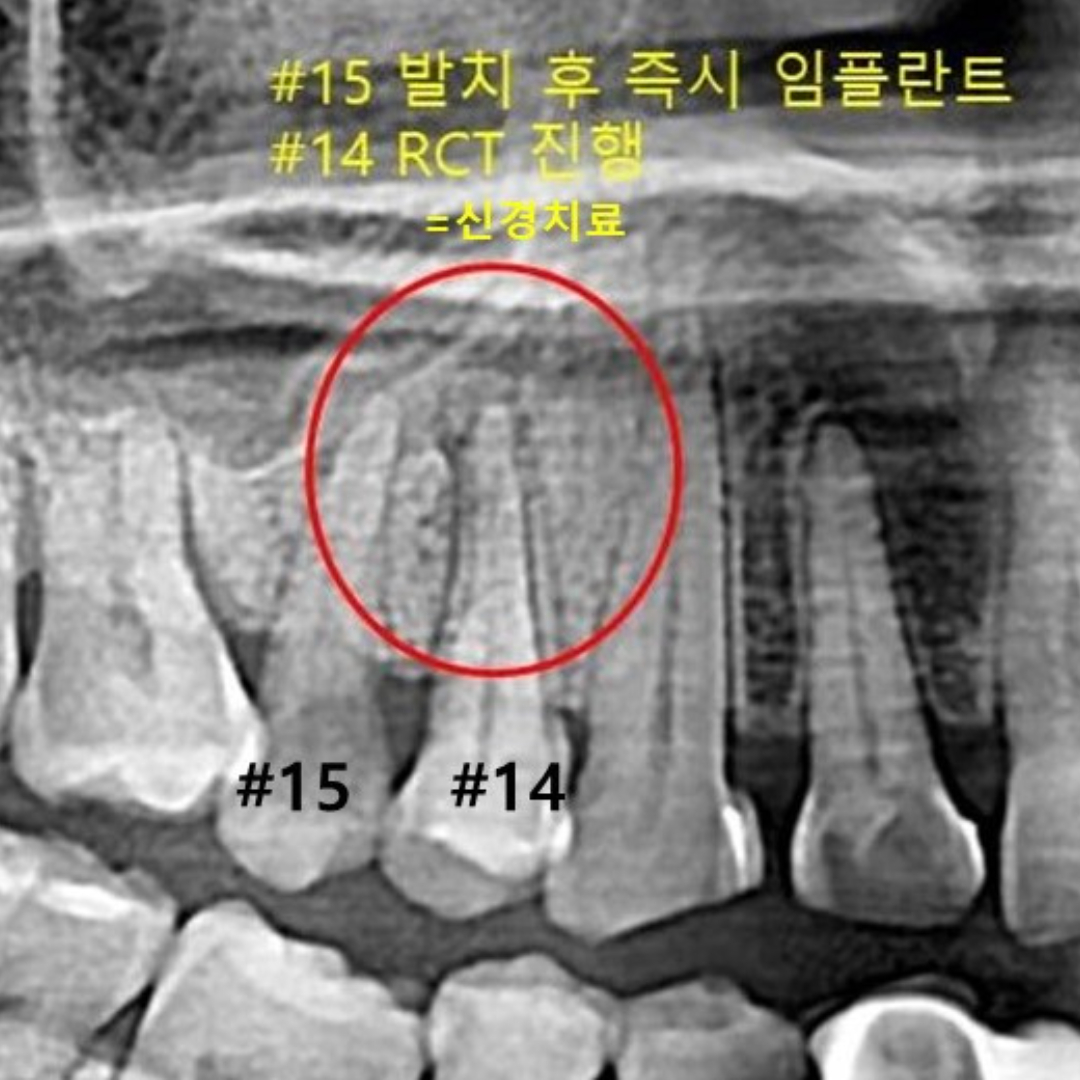

• 이백점 신경치료

• 서울대학교 치과병원

보존과 전문의가

충치부터 미세 신경치료까지

세심하게

• 본 컬럼은 56조 제 1항의 의료법을 준수하여 작성되었으며 실제 내원 환자분의 동의하에 공개된 치료과정의 사진이 포함되어 있습니다.

개인에 따라 진료 및 치료방법이 다르게 적용될 수 있으며, 효과와 부작용이 다르게 나타날수 있는점을 안내 드립니다.